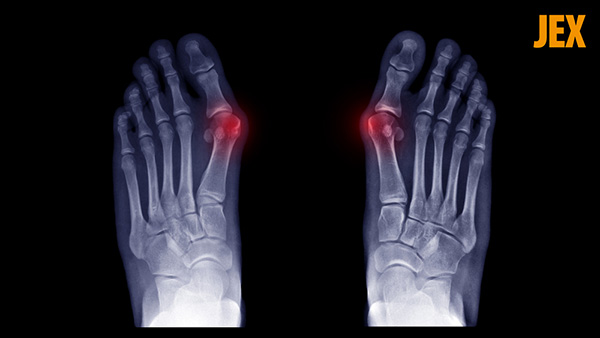

Viêm khớp ngón chân là tình trạng viêm các khớp ở bàn chân trước, trong đó khớp metatarsophalangeal (MTP) nối ngón chân cái với phần còn lại của bàn chân thường bị ảnh hưởng nhiều nhất.(1)

Kiểm tra hình ảnh: Người bệnh có thể được chỉ định chụp X – quang, cộng hưởng từ MRI hoặc CT scan để xác định cụ thể thành phần nào trong khớp đang bị tổn thương bởi phản ứng viêm. Ngoài ra, thông qua kiểm tra hình ảnh, bác sĩ có thể xác định mức được độ hư hại của sụn, xương dưới sụn, hệ thống mô mềm, sự bất thường của xương ngón chân.

Chụp X-quang chân giúp chẩn đoán viêm khớp viêm khớp ngón chân